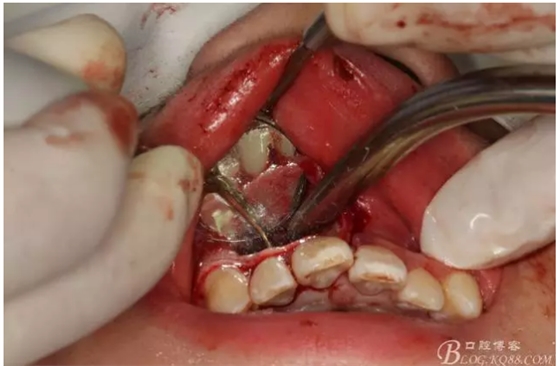

圖6.超聲骨刀切除根尖3mm。

圖7.切除根尖3mm的影像

圖8.根尖區(qū)超聲倒預備3mm